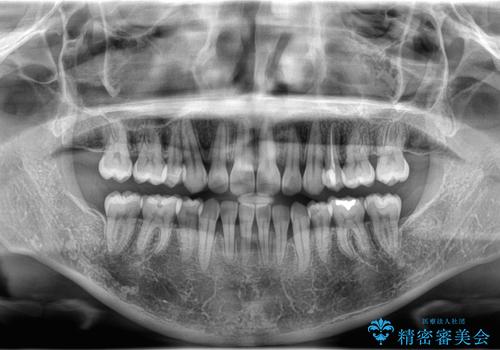

- 「歯のデコボコと前歯が出ているせいで口が閉じにくい」を主訴に来院された患者様です。

上下左右の4番(第一小臼歯)を抜歯をし審美ワイヤー装置で治療を行いました。

抜歯矯正により歯列のデコボコ(叢生)が改善し、前歯の突出も解消されたことで口元が下がり、すっきりとした印象となりました。